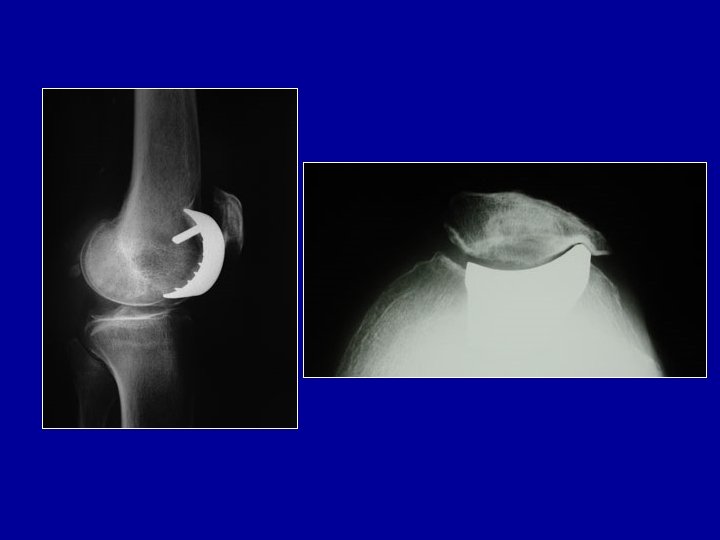

Arthrose fémoro-patellaire développée sur une ancienne luxation de la rotule (noter l’ossification volumineuse sur l’aileron interne) Traitement par transposition de la tubérosité tibiale et régularisation de la rotule